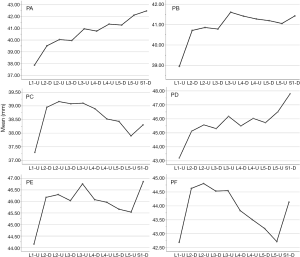

In the medium group, PC path was the shortest (38.56±3.25 mm), PA path and PB path had little difference (P=0.123), and there was no statistical significance. In the full-length group, PF path was the shortest (43.86±3.09 mm), and there was no significant difference between PD path and PE path (P=0.177) (Figure 10). All the paths increased successively from L1 to S1, among which PA and PD paths were the most obvious, followed by PB and PE paths. PC path and PF path first increased and then decreased (Figures 11,12).

The angles of each path (Table 2)

The included angles a1, a2, a3, b1, b2, b3 and c1, c2 and c3 in the sagittal plane were significantly different (P≤0.001) (Figure 13) (a1 > a2 > a3, b1 > b2 > b3, c1 < c2 < c3). In the angles of sagittal down-path, b1, b2 and b3 change significantly and consistently, showing a trend of decreasing first and then increasing, which is the smallest at L3 (46.08±4.37°, 36.21±3.51°, 22.47±3.01°) and the largest at S1 (69.49±8.28°, 61.23±7.74°, 36.60±5.00°). In the angles of sagittal up-path, a1 and a2 change in the same way, showing an increasing trend. While a3 goes down and then goes up, which is the smallest at L4 (23.43±4.29°) and the largest at L5 (24.36±2.94°). In the angles of axial plane, c1, c2 and c3 change in the same way, showing a trend of increasing first and then decreasing. c1 and c2 are the largest at L2 (40.07±2.75°, 55.1±3.32°), and c3 is the largest at L3 (73.11±2.10°). c1, c2 and c3 are the smallest at S1 (33.87±2.94°, 47.92±3.54°, 67.15±3.60°) (Figures 14,15).